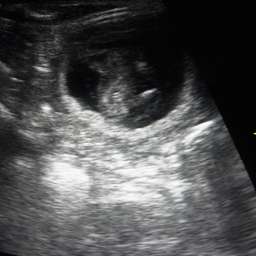

9.4.2015, 32.Tag: "Lieber Fiete! Ich habe gute Nachrichten für Dich: Du wirst Vater. Unser Date blieb nicht ohne Folgen.

5 kleine gesunde Wunder mit pochenden Herzen haben wir im Ultraschall gesehen. Freust Du Dich? Deine Adele"

Adeles Bauchumfang ist aktuell 45cm. Also 3cm Wachstum in 4 Tagen. Gewicht: 6,6Kilo. Oho, jetzt geht es los...!!!

Adeles Wunder

Adele hat den Ultraschall übrigens super gemeistert. Kahlrasur am Bauch hat sie abgelehnt. Aber ansonsten war sie ziemlich entspannt und in Vorfreude auf ihre Fleischwurst.